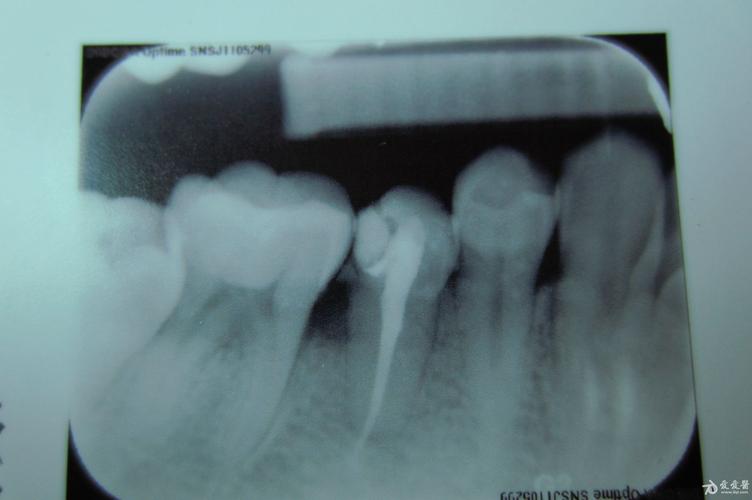

根管治疗前后牙片,求助!

根管治疗后的牙片,,求诊断.

之前在诊所做完根管治疗后,拍了牙片,医生说充填过细而且有超充,很有